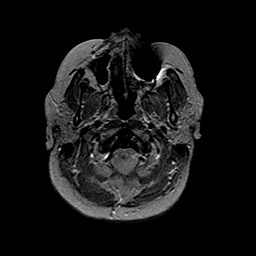

MR Study #2 -- Slice #5